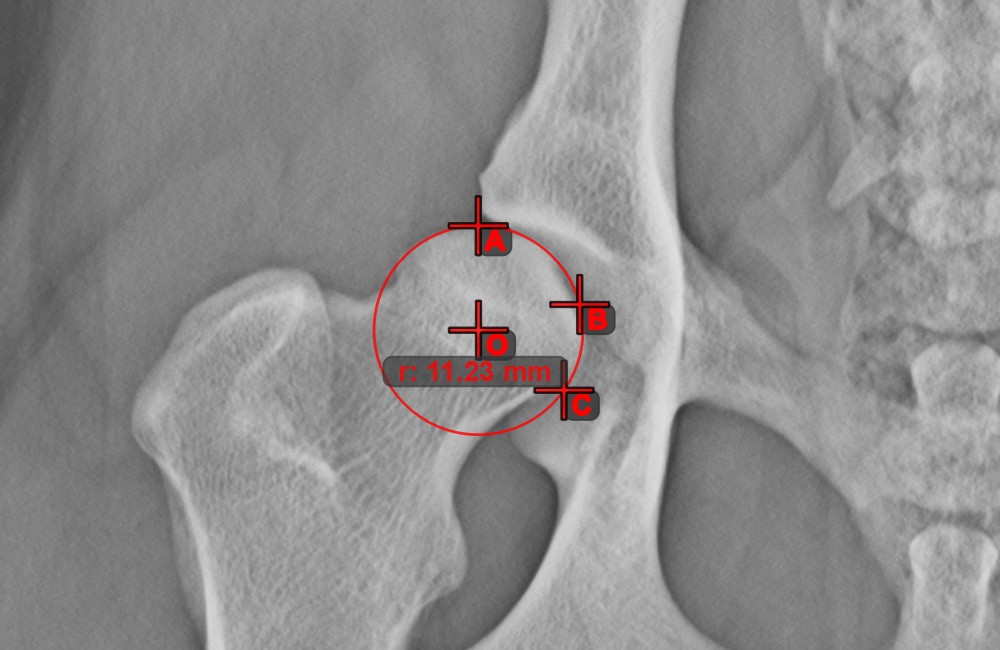

Circle from 3 Points

../_images/image69.jpg

The Circle from 3 Points tool is a simple and effective way to create a circle from just three points.

Start by selecting the tool from the left toolbar and assign it to one of the available mouse buttons. Place the three points of the circle, or select the points from ones available on the scene. The circle will be automatically created based on the position of the three points. The origo of the circle will always be marked with O. The radius of the circle is automatically calculated.

Modify the position of the three points to change the radius of the circle by using the Select/Move Item tool.

../_images/image108.jpg